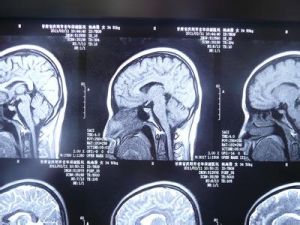

3、影像學檢查可確診。CT表現為額顳頂部新月狀低密度區,常進入縱裂前部,腦組織受壓,CT值為0—10Hu。

血腫T1和T2一般為高信號,積液與腦脊液信號一致,表現為T1低信號,T2高信號,即可鑑別。